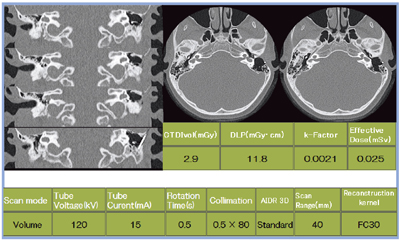

人工内耳を使用している女児の例では,水晶体を避けて,40mm幅0.5s/rot,1volumeで撮影し,CTDIvol 2.9mGy,DLP 11.8mGy・cm,線量0.025mSvと,低線量での撮影を実現している(図4)。

図4 Volume Scanの適用例